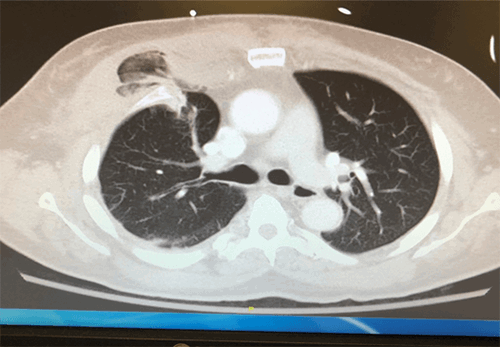

A 59-year-old man was transferred to our level 1 trauma center from a nearby emergency department. He was involved in a motor vehicle collision ten days earlier but was found to have no injuries at that time. Since the collision, he developed worsening chest pain and coughing. His symptoms continued to decline until an episode of hemoptysis brought him to the outside emergency department for evaluation. A CT scan was performed at that time which demonstrated right pulmonary herniation and first through fifth costal cartilage fractures (Figure 1). He was transferred to our Level 1 trauma center for escalation of care. Once at the trauma center, there was fullness in the antero-medial aspect of the right chest wall on examination. The decision was therefore made to take him to the operating room for a right thoracotomy.

Figure 1. Right lung herniation with ribs 1-5 costal cartilage fractures